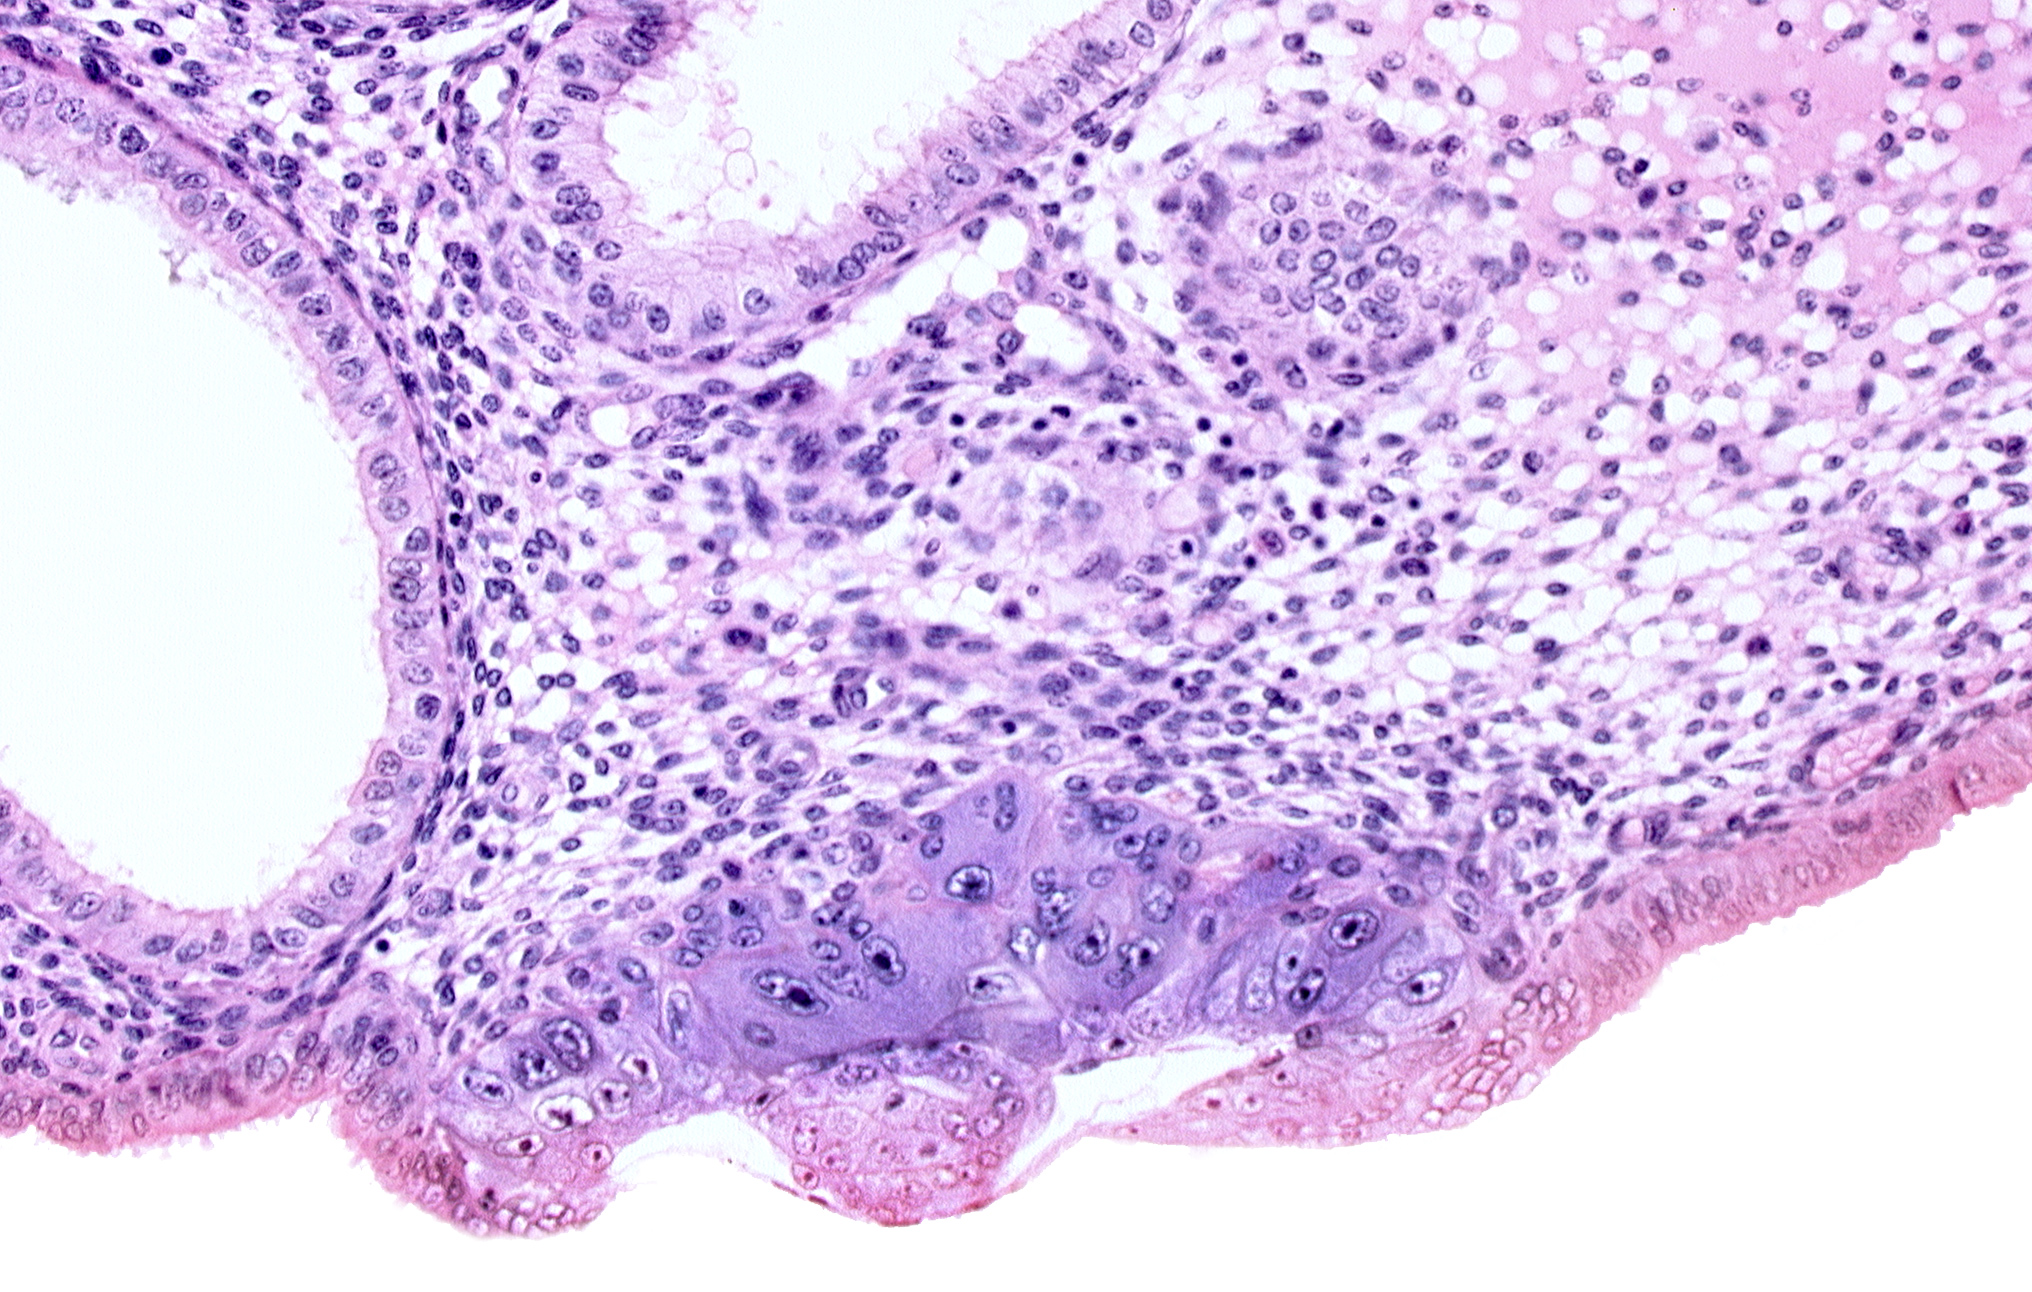

Carnegie Embryo #8020 | Location: 06-02-02

Keywords: amniotic cavity, blastocystic cavity (blastocoele), embryonic disc, endometrial epithelium, endometrial sinusoid, membranous trophoblast at abembryonic pole

Source: The Virtual Human Embryo.